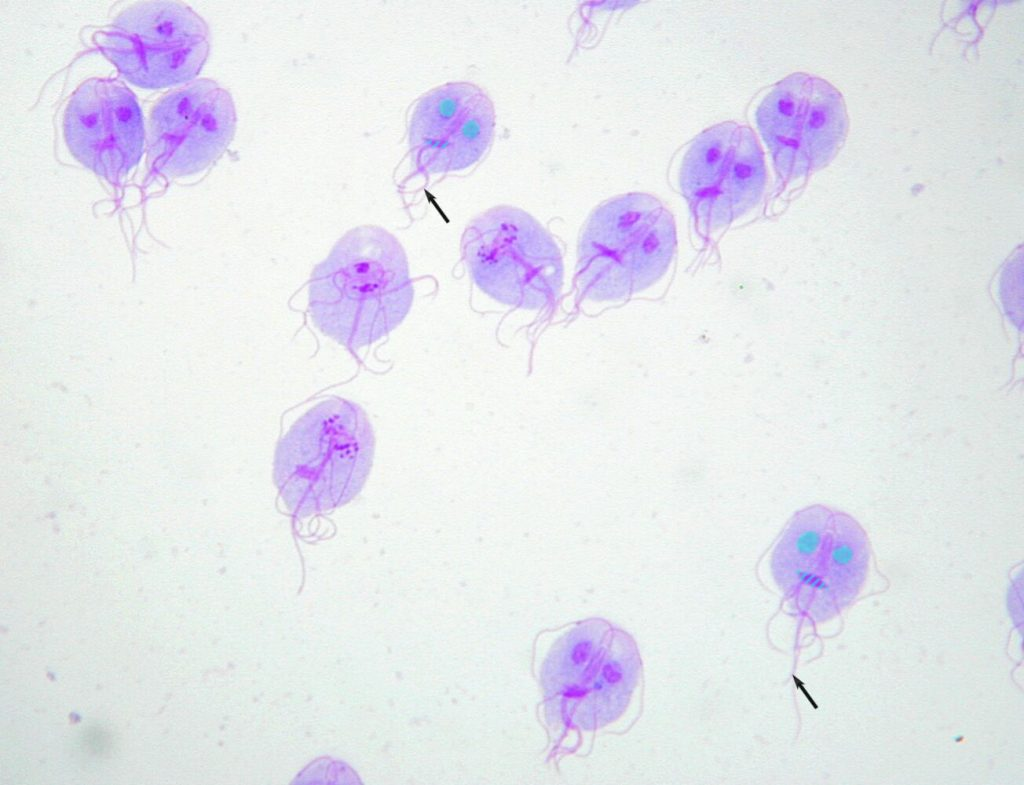

giardia intestinalis trofozoity

giardia intestinalis trofozoity